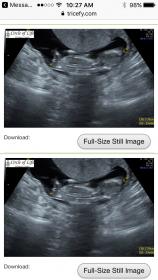

13 weeks please help!!!

So this is for my sweet sister in law!! I know they aren't ideal position of baby! But I thought maybe I could still get some thoughts!!! My sweet sister in law already has 3 babies of one gender and this is her last baby and is hoping for the opposite.gender! And I also fixed the link to the better images!!!! Attachment 36153 or here is a link to them https://tricefy.com/link/ahh7t1v11yr8

Hmm. I can't explain why I'm giving a girl guess, but I am! Even though the baby is on his/her back, it's like a potty shot view of between the legs. If these are your only pics, I'm giving a slight girl guess. I'm not entirely confident on this though!

My first thought was girl too but I'm hoping I'm wrong. She has 3 girls already and this is her last baby. She would really like a boy but will not be devastated if it's another girl!!! With MY last baby (I have 3 boys and did a strict sway for a girl) THEY told me I was having my 4th boy at my ultrasound but I ended up having a girl!!! Anyway the bottom potty shot looks just like my daughters 14 week potty shot where I was incorrectly told boy.... I hope I'm wrong!